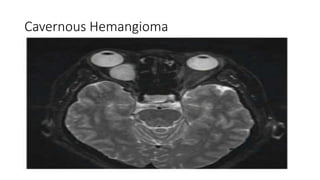

Cavernous Hemangioma